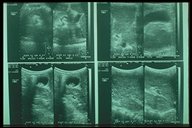

Ultrasonography of gall stones in children